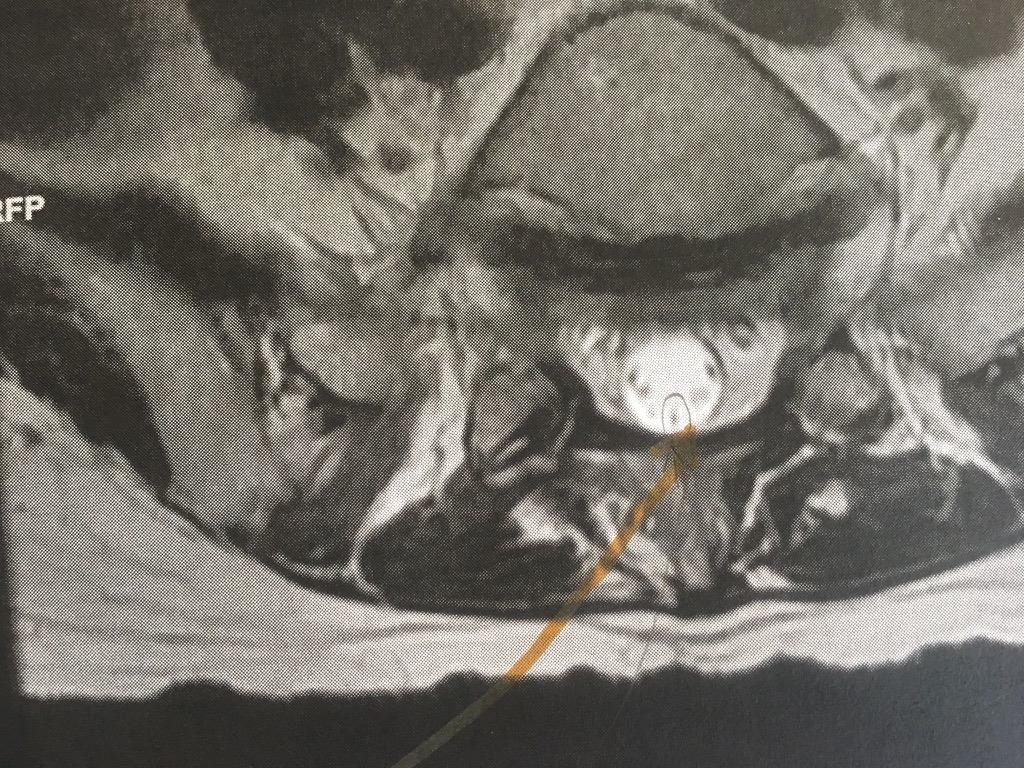

Another view of the tethered filum.